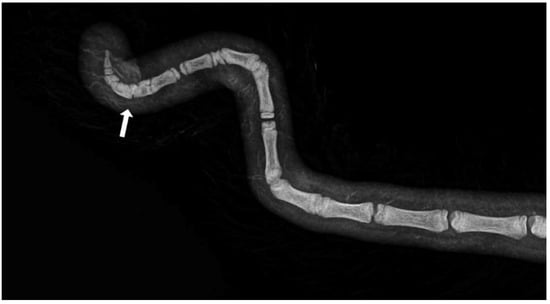

3.1. Measurements and Radiographic Examination